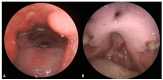

Drug-induced or associated vasculitis is a prevalent form of vasculitis that resembles primary idiopathic antineutrophil cytoplasmic autoantibody (ANCA) vasculitis (AAV). Cocaine is a diffuse psychostimulant drug and levamisole is a synthetic compound used to cut cocaine. Their abuse may result in a spectrum of autoimmune manifestations which could be categorized into three overlapping clinical pictures: cocaine-induced midline destructive lesion (CIMDL), levamisole-adulterated cocaine (LAC) vasculopathy/vasculitis, and cocaine-induced vasculitis (CIV). The mechanisms by which cocaine use leads to disorders resembling AAV are not well understood. Cocaine can cause autoimmune manifestations ranging from localized nasal lesions to systemic diseases, with neutrophils playing a key role through NETosis and ANCA development, which exacerbates immune responses and tissue damage. Diagnosing and treating these conditions becomes challenging when cocaine and levamisole abuse is not suspected, due to the differences and overlaps in clinical, diagnostic, therapeutic, and prognostic aspects compared to primary idiopathic vasculitides.